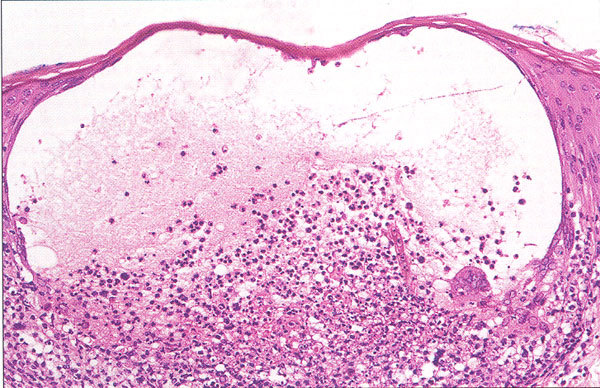

HSV Histology

Multinucleation

Ballooning Degeneration

Tzanck Cells

HSV Histology –> Ballooning Degeneration

Acantholysis (separation of keratinocytes)

Nuclear clearing

Nuclear enlargement

Free floating (clump of cells) epithelial cells

Cells detached

Caused by acantholysis